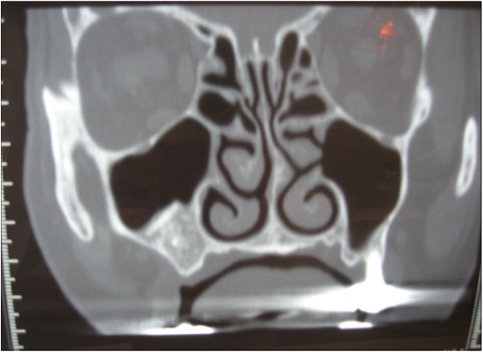

Dans les cas de perte osseuse prémolaire et surtout molaire au maxillaire, une augmentation osseuse est possible au niveau des sinus maxillaires : c’est ce que l’on appelle le sinus lift.

Le principe est d’ajouter un volume osseux suffisant sous les futurs implants pour que ceux ci ne soient pas dans le sinus maxillaire.

Dans certains cas, si l’os résiduel est suffisant des implants peuvent être placés dans le même temps.